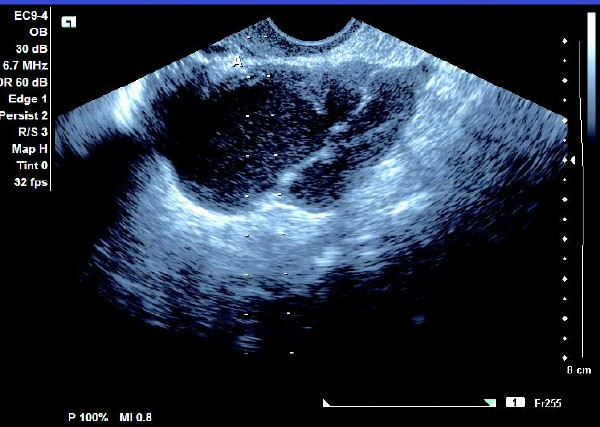

(1)单侧或双侧卵巢内呈现椭圆形或圆形无回声暗区,其内充满弱回声光点,囊肿直径一般为5~6 cm,大于10 cm 的较少见。

(2)壁较厚,囊内充满细小均匀点状回声,后方回声增强。

(3)常与周围组织有粘连,边界清晰。

患者,女,35岁。每次月经量少,痛经,近来行经期延长、疼痛加重来院诊治。超声报告显示子宫前倾位,子宫体大小为:5.9cm×5.1cm×4.8cm,形态规则,边界清晰,宫避回声匀称,宫腔线居中,内膜厚度0.6cm,宫内未见异常回声。右侧卵巢内可见大小约5.2 cm×4.9cm的无回声区暗区,壁厚,内壁欠光滑,内见密集细光点,边界清晰。CDFI探测囊壁及囊腔内无血流信号。

超声提示:右侧卵巢巧克力囊肿